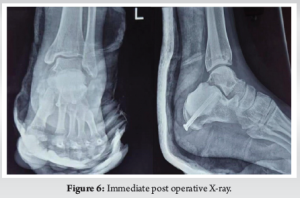

A 27-year-old female presented to OPD with complaints of swelling and tenderness in the lateral aspect of the left ankle and foot for 3 months. There is a history of twisting injury to the left ankle while riding a bicycle 3 months back, after which the patient noticed the swelling. The patient has received conservative management for lateral ankle sprain but, however, no radiographs were taken during such consultations. On clinical examination, there was a diffuse swelling involving the lateral aspect of the left ankle (Fig. 1) which was tender on palpation without any local rise of temperature. There is no history of any constitutional symptoms. Ankle and foot examination are within normal limits. On roentgenography (Fig. 2), we found an expansile, lytic lesion in the proximal aspect of the body of the left calcaneus. The lesion has a narrow zone of transition. There was no periosteal reaction, no matrix, no soft-tissue component. There was no sclerotic margin. Multiple septae appear to be traversing the length of the lesion, producing a trabeculated appearance. Radiologic evaluation of other body parts ruled out multicentric lesions.